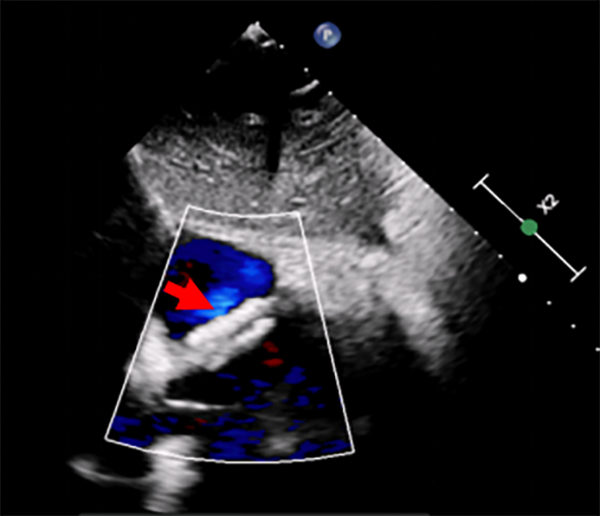

第1例手术患者为一名5岁6月、患有室间隔缺损的儿童,超声心动图提示膜周部室间隔缺损约4mm,缺损上缘距离主动脉右冠瓣无残端,右冠瓣轻微脱垂,若采用传统的金属封堵器介入封堵,术后发生心律失常、主动脉瓣返流等并发症的几率偏高。第2例手术患者为一名8岁伴反复头痛1年、患有卵圆孔未闭的儿童,经药物治疗无效,超声心动图提示卵圆孔未闭2mm。

卵圆孔未闭封堵